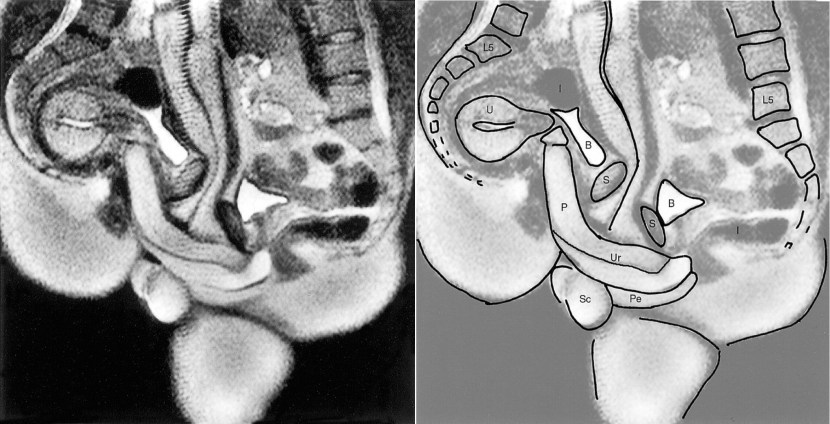

Tomography of sexual intercourse